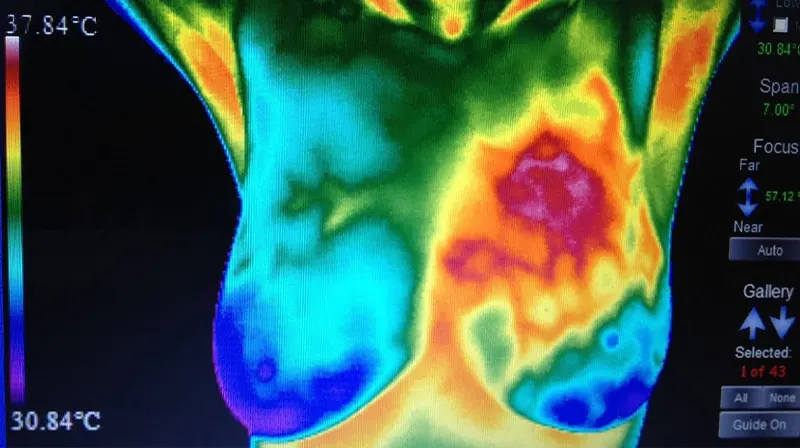

Breast Cancer Screening: Thermogram No Substitute for Mammogram

August 2020

Dr. Cyrus Khorrami, MD